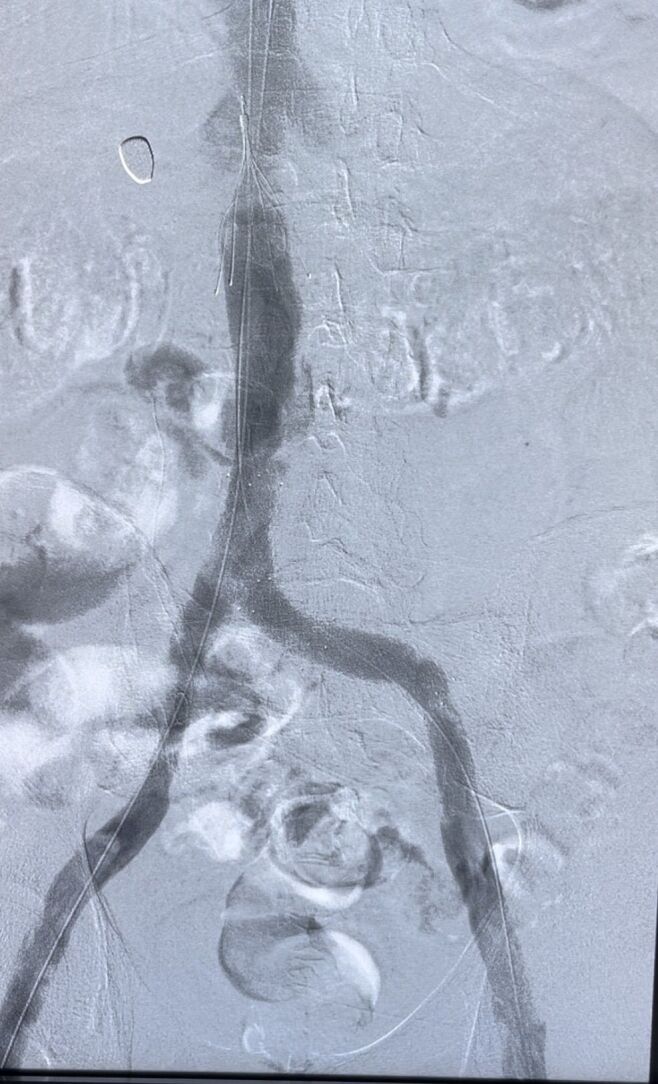

Vena cava filters are used to treat deep vein thrombosis and pulmonary embolism. Despite the extensive literature on these filters, there is still no reliable evidence that they improve clinical results or mortality in patients with deep vein thrombosis. There are also increasing reports of complications from indiscriminate use, with a complication rate of approximately 19%. Complications include penetration into the vein wall, involvement of adjacent organs, fracture, embolization of filter fragments, and deep vein thrombosis. We describe the successful removal of a vena cava filter 4 years after implantation for inferior vena cava thrombosis. The procedure was performed using common endovascular surgery devices.